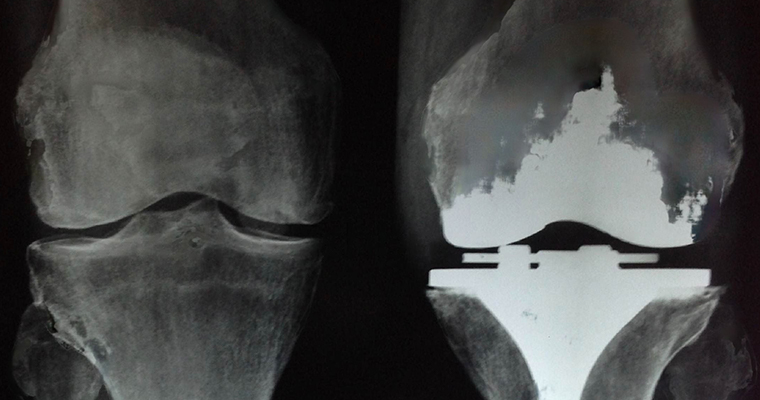

Joint replacement aims to restore painless motion to a joint and function to the muscles, ligaments, and other soft tissues that control the joint. Either a part or the total damaged bone is removed and replaced with artificial components made out of metal and polyethylene and the bones of the joint are "realigned" so that the weight that passes through the joint is normally distributed. Hip and knee the major weight bearing joints are the most commonly affected joints and are commonly replaced. Ankles, shoulders, elbows, wrists and fingers can also be replaced.

Joint replacement relieves pain, restores function and the newer type of joints allows unrestricted activities.